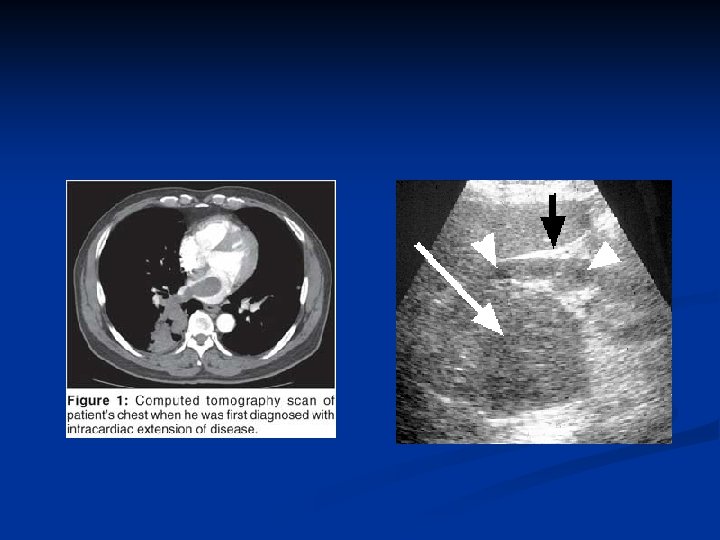

Investigations Diagnosis can often be confirmed by renal ultrasound n CT scanning allows assessment of renal vein and caval spread n Echocardiogram should be considered if clot in IVC extends above diaphragm n

RCC with IVC thrombus